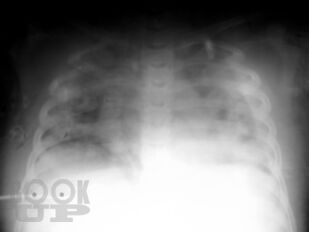

В учебно-методическом пособии представлены этиология, патогенез, клиника, осложнения, лечение, комплексная ультразвуковая, рентгенологическая, мультиспиральная компьютерная томографическая семиотика острого гематогенного остеомиелита у детей. Пособие раскрывает современные подходы ранней диагностики острого гематогенного остеомиелита у детей и предлагает оптимальный алгоритм ранней диагностики.